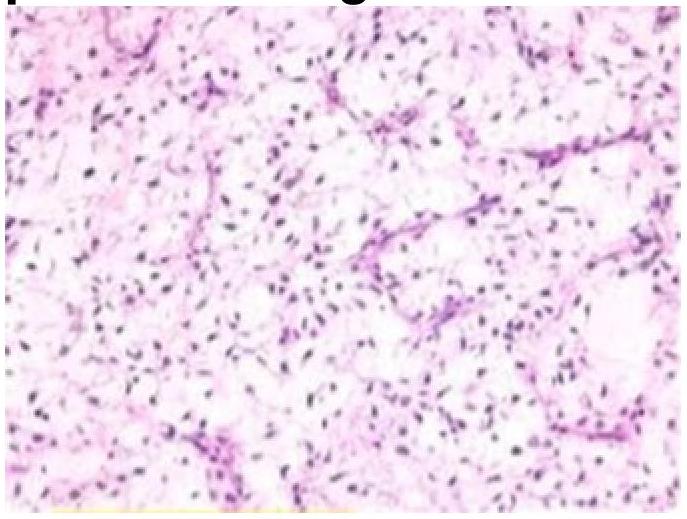

Question 6: A 5-year-old child presented with a history of blood in the stools. On examination, there was a polypoid mass in the rectum, a biopsy of which showed as below. The most probable diagnosis is?

- B. Juvenile polyp (Correct Answer)

Explanation: ***Juvenile polyp*** - The image shows **dilated, cystically appearing glands** within an inflamed lamina propria, which is characteristic of a juvenile polyp. - Juvenile polyps are the most common cause of **rectal bleeding** in children under 10 years of age and are typically benign. *Villous adenoma* - Villous adenomas are **neoplastic polyps** with a **villous (finger-like) architecture** and are more commonly seen in older adults [1]. - They typically show **dysplastic changes** and are considered premalignant [1]. *Vascular malformation* - Vascular malformations consist of **abnormally formed blood vessels** (e.g., arteriovenous malformations, hemangiomas) and would appear as dilated or aberrant vessels on histology. - While they can cause bleeding, the image does not show a predominance of vascular structures. *Serrated adenoma* - Serrated adenomas are characterized by **sawtooth-like glandular infoldings** and show varying degrees of dysplasia. - They are typically found in adults and are considered premalignant, not benign growths usually found in children. **References:** [1] Cross SS. Underwood's Pathology: A Clinical Approach. 6th ed. Common Clinical Problems From Alimentary System Disease, pp. 371-372.